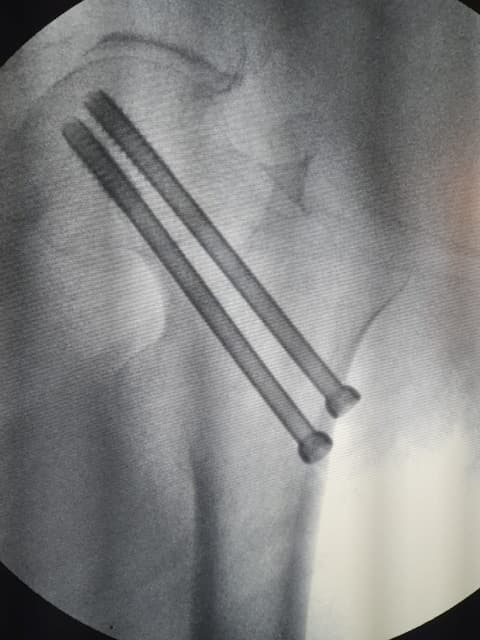

Periprosthetic fracture-Хиймэл үе суулгасны дараах хугарал

Хугарал засах мэс засал image10Хугарал засах мэс засал image11

Өвчтөн Б 52 настаЙ эмэгтэй 2020 оны 04 сард дунд чөмөгний хүзүүний эмгэг хугаралын улмаас түнхний үеийг бүтэн солих мэс засал хийлгэсэн. Мэс заслын дараах 25 дах хоног дээр явганаас халтирч унаж дахин хугаралыг зассан үеийн рентген зураг